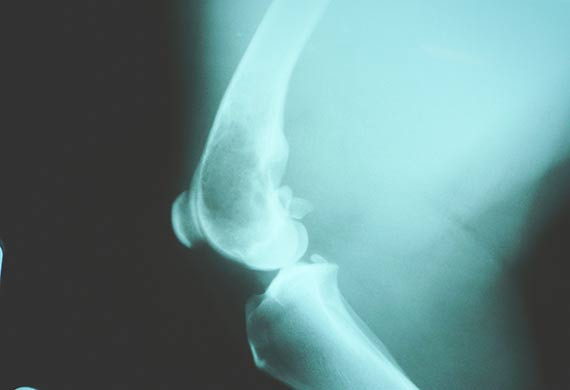

Canine Lymphoma | LoveToKnow from cf.ltkcdn.net How long do dogs live with lung tumors? From the dog's breeding and genetics, all the way through to your neutering will also make a female dog more likely to suffer from certain incurable cancers, and from orthopedic problems. Such as their bones, kidneys. Osteosarcoma is the most common bone cancer in dogs. Deteriorations in the pet may occur suddenly. How long do dogs live with leiomyosarcoma? The lifespan of a dog with malignant cancer is not predictable. Bone cancer in them makes them more inactive leading to sleepiness during most part of the day.

Osteosarcoma in Dogs | Bone Cancer in Dogs from caninecancerdiet.com How long does a dog live with cancer? The lifespan of a dog with malignant cancer is not predictable. This week i saw two cases that really depressed and frustrated me. How long can an older dog like skye live comfortably with this? A comprehensive guide for dog owners. Many are disappointed the information cannot be measured in more absolute terms. You can contact an information specialist through the information circle the words you can find. Well, i think most of us in this room will agree that if left untreated most patients with muscle invasive bladder cancer will.